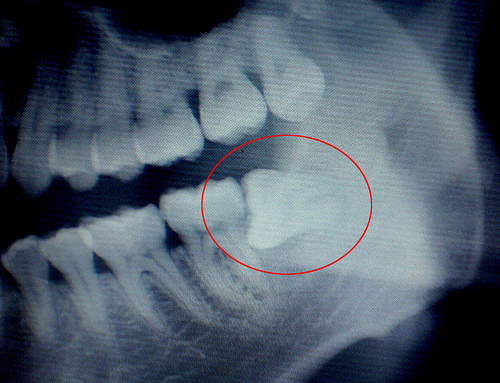

医生在进行拔牙前,对患者口腔进行全面的检查及诊断,如有炎症或龋病需要治疗时,那么则应进行相对应的治疗,这种情况下,拔牙价格则相对要贵些。另外有些患者的患牙病变较为严重或结构极为复杂,那么在拔牙前需要拍摄口腔全景片来了解的底部结构,因此这种情况下的拔牙,拔牙价格略有上升。

郑州唯美口腔微创拔牙新技术,通过西诺德口腔CT扫描机对患牙进行全面拍摄,确定患牙位置,然后实施局部麻醉后,在无菌条件下操作,微创拔牙技术操作时间短,减轻了患者拔牙过程中的不适感觉,缩短了手术时间,消除患者紧张恐惧的心理,具有创口小、出血少、痛苦轻、术后并发症少的优点,特别对复杂阻生智齿的拔除具有明显优势,避免了传统的劈冠凿骨和敲锤增隙,大大减轻了患者的不舒适感觉,使牙齿充分松动并轻松脱出。推荐阅读:郑州治疗智齿哪家医院好